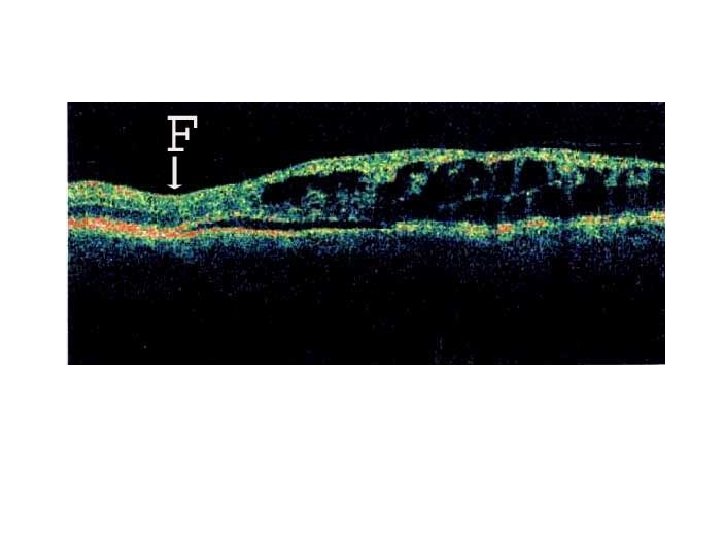

• Optical coherence tomography shows a neurosensory detachment involving the macula. • Note

• Optical coherence tomography shows a neurosensory detachment involving the macula. • Note the schisis cavity overlying the neurosensory detachment as well as the outer layer hole.

• Optical coherence tomography demonstrates a choroidal neovascular membrane and associated subretinal fluid

• Retinal pigment epithelium detachment